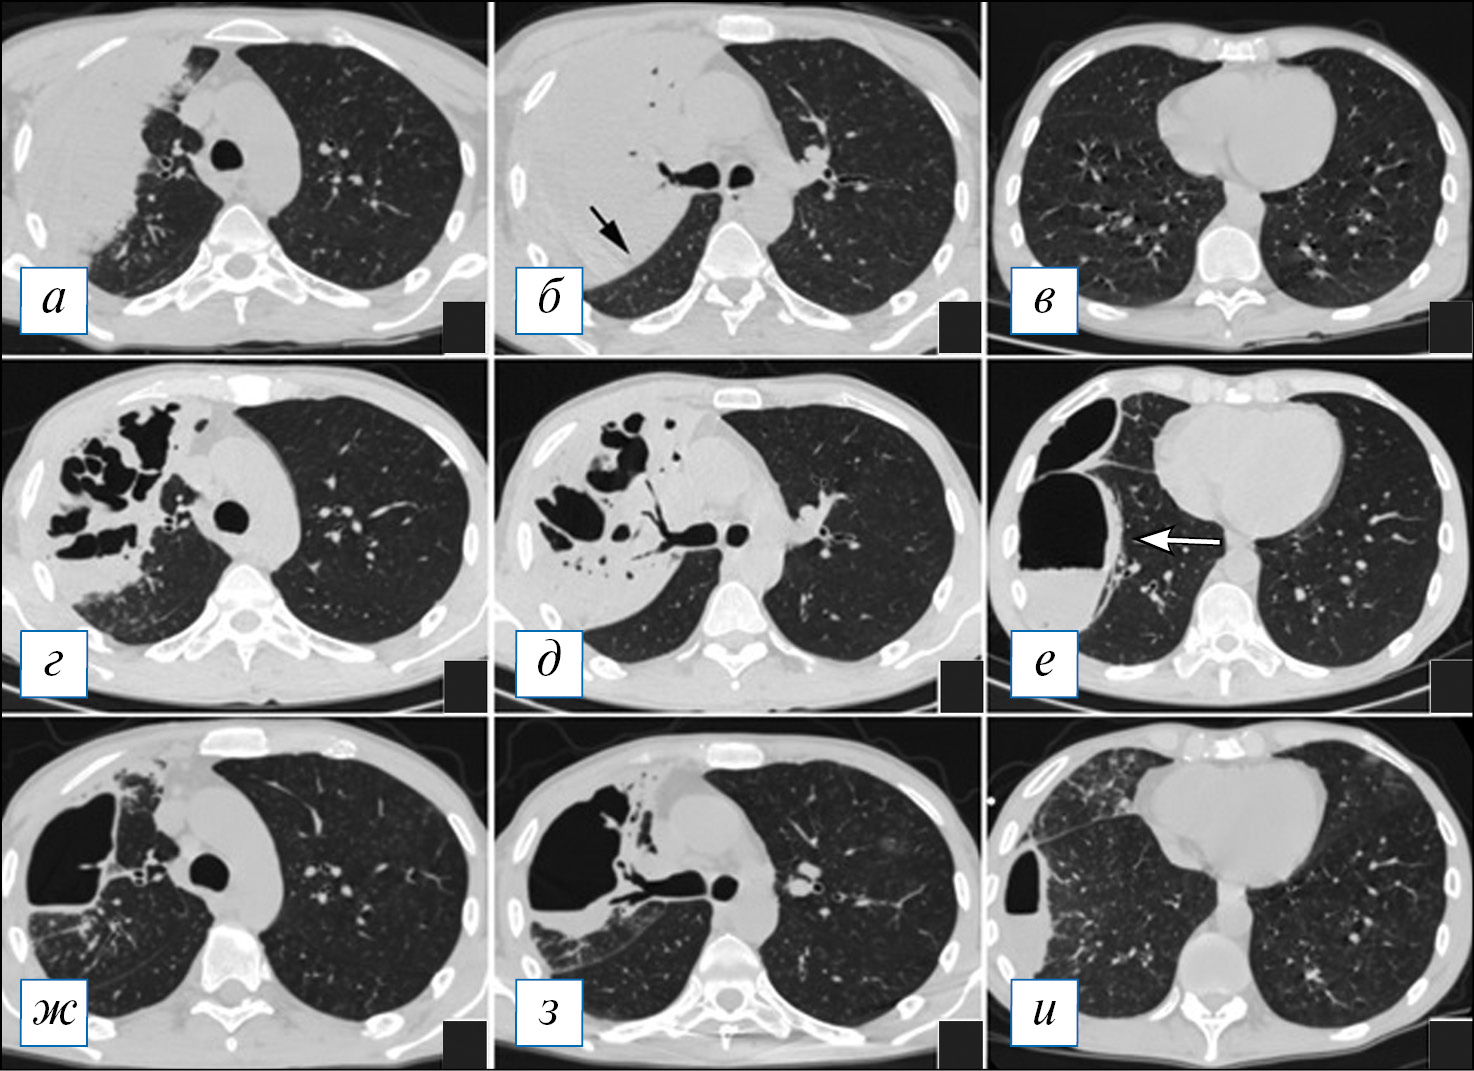

При проведении КТ органов грудной клетки отмечается уплотнение, чаще в виде консолидации или по смешанному типу, в сочетании с «матовым стеклом» пораженной части легкого, которая может быть несколько увеличена в размерах (рис. 2, Б), что объясняется скоплением экссудата и отеком легочной паренхимы по типу «выбухающей борозды». На фоне уплотнения быстро происходит деструкция легочной ткани в виде множественных очагов или более обширных участков; в начале этого процесса в полостях распада можно наблюдать некоторое количество содержимого с горизонтальным уровнем; секвестры нехарактерны (рис. 2). Внутренняя стенка полостей имеет четкий контур, что объясняется дренированием содержимого через бронхи, которые в ряде случаев прослеживаются (рис. 3). Может отмечаться выраженная реакция плевры, с развитием выпота или даже эмпиемы и пиопневмоторакса, особенно при формировании свища [8, 9, 40]. Негативными последствиями некротизирующей пневмонии может являться формирование фиброза с бронхоэктазами, персистирование полостей распада при отсутствии их спадения, а также облитерация плевральной полости на уровне воспалительного процесса [39].

Рис. 2. Компьютерная томография органов грудной клетки в аксиальной проекции (а–г). Двусторонняя полисегментарная пневмония. С обеих сторон в легких, больше справа, имеются инфильтраты, на фоне которых просматриваются полости различного размера без жидкостного содержимого. Незначительный пневмомедиастинум. [Изображения из архива авторов]. / Fig. 2. Chest CT, axial projection (а–г). Bilateral polysegmental pneumonia. On both sides in the lungs, more to the right, there are infiltrates and cavities of various sizes without liquid content. Minor pneumomediastinum. [Images from the authors’ archive].

Рис. 3. Компьютерная томография органов грудной клетки в аксиальной проекции (а, б). Пневмоническая инфильтрация в верхней доле слева с деструкциями. Имеются участки по типу «шальной исчерченности» в сочетании с консолидацией, на фоне которой обнаруживаются разнокалиберные полости распада без содержимого, наружный их контур не прослеживается. [Изображения из архива авторов]. / Fig. 3. Chest CT, axial projection (а, б). Pneumonic infiltration in the upper lobe on the left with destructions. There are areas of a «crazy paving» sign in combination with consolidation, against the background of which one can see destructive cavities of various sizes without content, their outer contour is not traced. [Images from the authors’ archive].